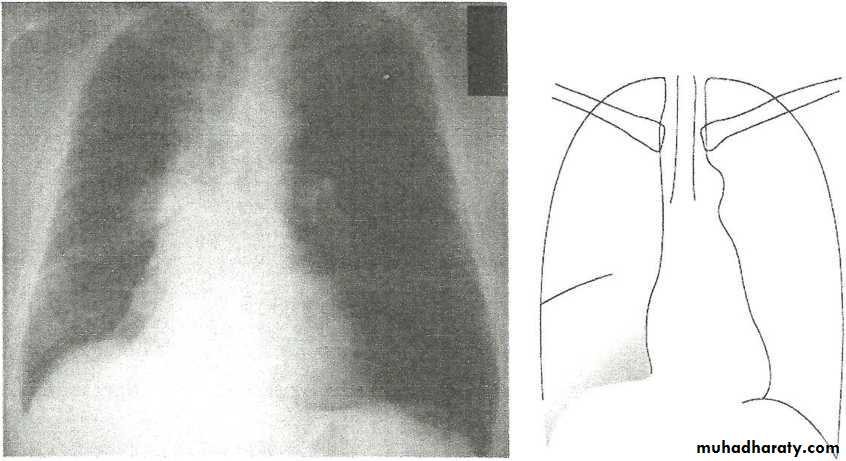

• LOBAR PNEUMONIA

Right lower lobe consolidation - PA. Dense opacification in the right lower zone with effacement of the outline of the right hemidiaphragm.

• Right lower lobe consolidation - Lat.

• The density lies posterior to fthe oblique issure- the position of the lower lobe.